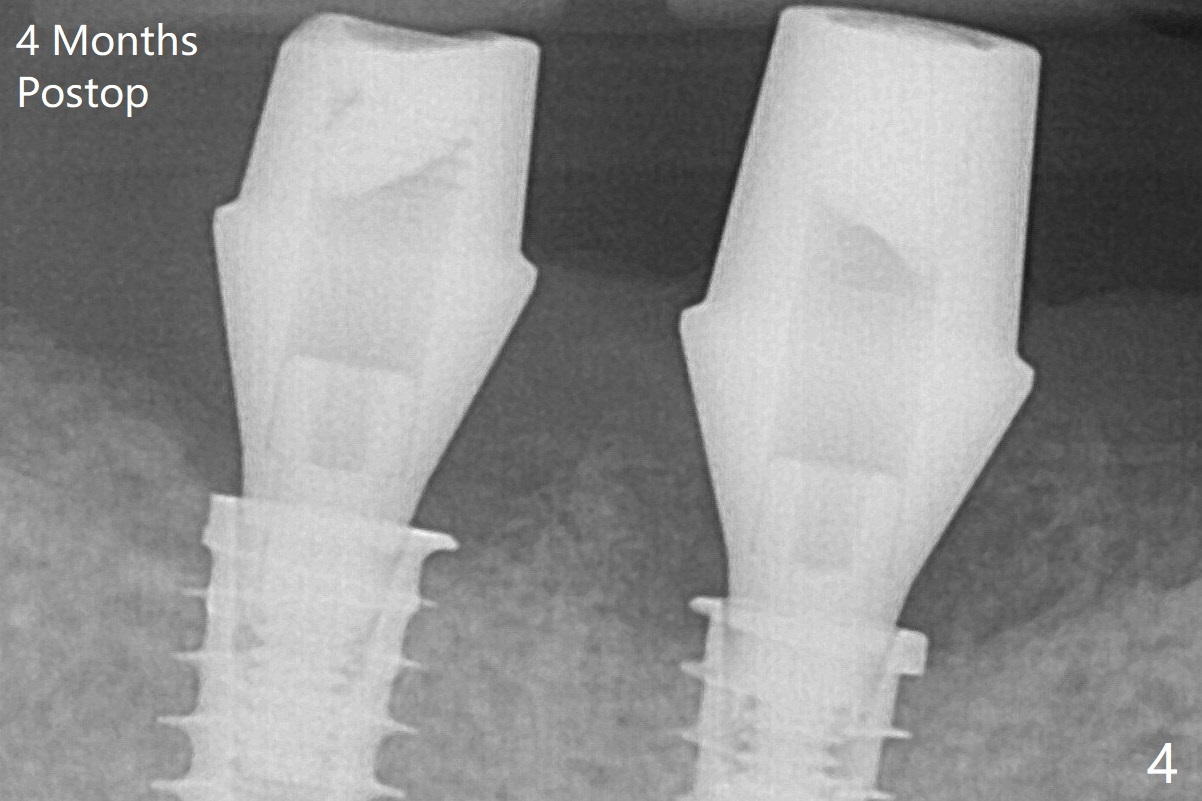

Note bone growth, especially at #30, 2.5 and 4 months postop (Fig.3,4). In fact the abutments are incompletely seated. The crown of #30 is loose with foul smell 2 years 8 months post cementation. It is painful to reinsert the crown/abutment after proximal reduction. A healing abutment is placed (Fig.5). When the incompletely seated abutment at #31 is removed, there is also smell. After separation from the crown, the abutment of #31 returns to the site with change in insertion position, while a smaller abutment has to be used at #30 (Fig.6) due to use of the small healing abutment earlier (Fig.5). A good piece of news is the presence of the bone between the implants (Fig.5,6 *), which contributes to interimplant papilla.